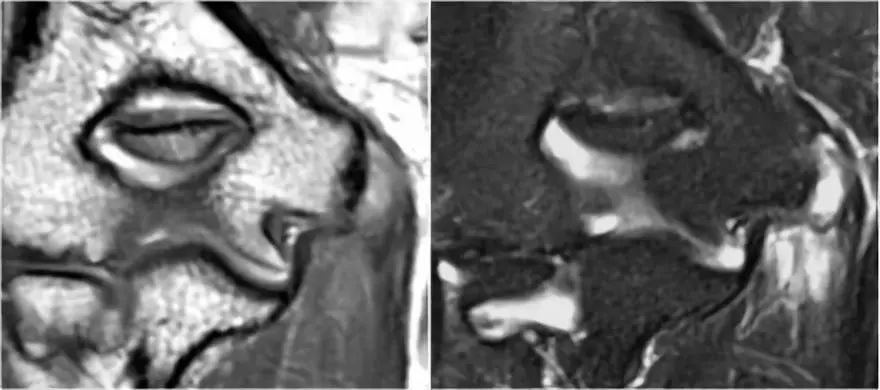

易混淆的影像

1.假的小凸起这是我们经常在冠状图像上看到。它看起来像是一个骨软骨病变,但是如果看一下矢状位图像,就会发现冠状图像穿过了髁骨的后关节部分,因此,当肘完全延伸,桡骨小头的一部分实际上是肱骨小头的后面。

在冠状视图上,我们将看到被软骨覆盖的桡骨头,并且与髁骨头的非软骨覆盖部分相对,其通常有些不规则。

2.假游离体另一个常见的发现是你在矢状图上看到的一小块脂肪,看起来像一个小游离体或软骨缺失。如果我们观察鹰嘴的关节面,可以解释这一点。鹰嘴通常有两片软骨,中间有一小块软骨,里面充满了脂肪。

3.滑膜皱襞(plica)有时可以看到关节外侧的这种结构并且是一个皱褶。它可以是突出的,几乎看起来像半月板。这是一种正常的结构,但有时它会变厚或不规则,可能是症状的原因。